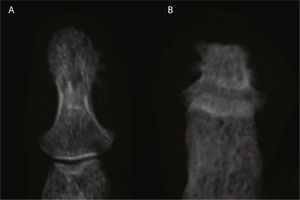

Presentación clínicaVarón de 30 años de edad, diagnosticado de hipertensión arterial pulmonar primaria sin cortocircuito asociado a los 2 años de edad, en seguimiento por Cardiología Pediátrica desde entonces. No tenía otros antecedentes médicos personales ni familiares de interés, incluyendo enfermedades reumáticas y psoriasis. A los 29 años comenzó a presentar episodios de poliartritis simétrica y aditiva que afectaban rodillas, tobillos, hombros, carpos y metacarpofalángicas, con importante limitación funcional. En la exploración física destacaba además la presencia de cianosis generalizada y acropaquias, sin lesiones cutáneas ni ungueales sugestivas de psoriasis. En la analítica se evidenció reactantes de fase aguda normales, factor reumatoide negativo y anticuerpos anti-CCP positivos a título bajo en una determinación aislada. El estudio radiográfico mostró acro-osteolisis en falanges distales de manos y pies, más severa en esta última localización, en la que algunas falanges adoptaban una morfología piramidal o con el extremo aplanado, y en ambas localizaciones existía importante neoformación ósea, más marcada en manos (figs. 1 y 2). En ambos carpos se observaba además pinzamiento radiocarpiano y de articulaciones intercarpianas, mayor en el izquierdo, sin erosiones. En huesos largos (tibias, peronés y radios) se evidenciaban corticales de aspecto algodonoso y despegamiento perióstico compatibles con periostitis. La gammagrafía ósea mostraba moderada hipercaptación en falanges distales de ambas manos, así como carpo y radio derechos y zona teórica de semilunar izquierdo.

Radiografía de manos (A) en la que se observa reacción perióstica en radio. Ensanchamiento distal con cambios hipertróficos en los penachos y áreas de osteolisis en los mismos, de las que es un buen ejemplo el cuarto dedo de la mano derecha. Desmineralización yuxtaarticular. Radiografía de pies (B) en la que se observan marcados cambios destructivos en falanges distales, algunas con morfología aplanada y penachos distales hipertróficos con proliferación ósea. Marcada deformidad de los dedos en palillo de tambor.